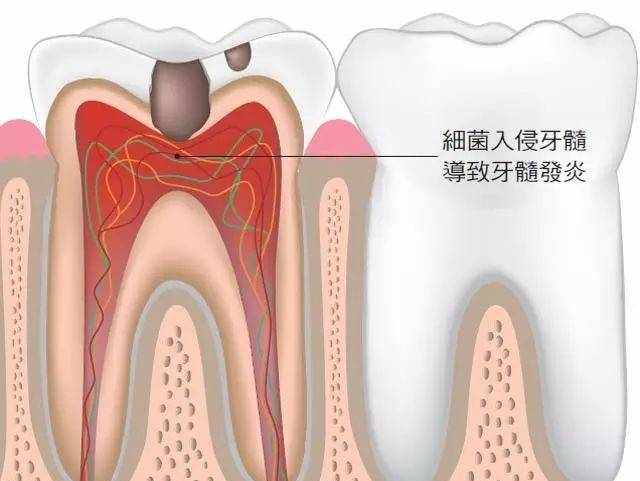

此时龋洞需要进行充填,否则会继续被侵蚀,导致牙神经损伤甚至牙神经死亡,感染或发生脓肿。因此,牙神经损伤需要进行根管治疗。

牙髓炎

如果此时依然没有及时治疗,龋坏里的细菌会入侵牙神经。

这会导致:牙神经发炎,牙齿出现自发疼痛,并且逐渐加剧,重者夜间睡眠受到影响,需要口含冷水才能使疼痛稍有缓解。

此时,疾病的名称为牙髓炎。

疾病至此,如果患者仍旧未及时治疗,牙神经内的细菌会继续向深层入侵,到达牙根的根尖区域,此时称为根尖周炎。

患牙的自发疼痛减弱,牙根区域出现跳痛,牙齿咬合疼痛,并出现患牙伸长浮起的感觉。